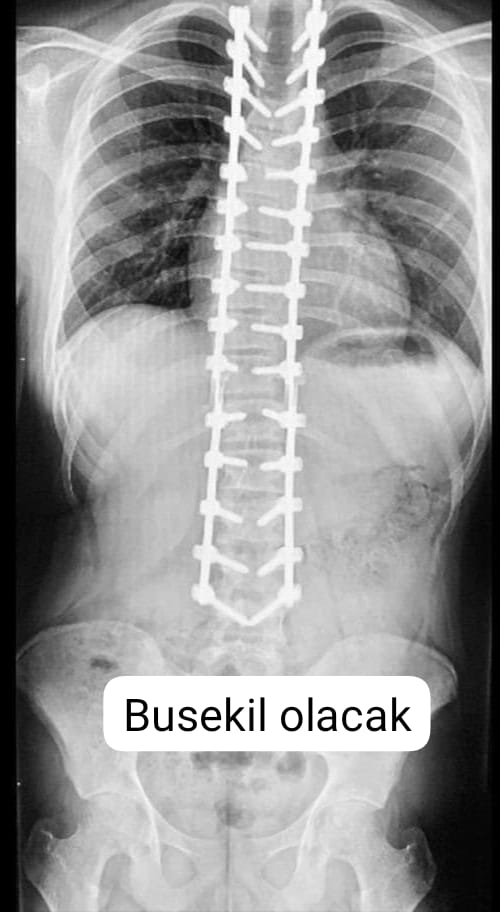

Skolyoz hastası (omurga eğriliği) Ecrin Selim, ameliyatla sağlığına kavuşacak. İstanbul'daki özel bir hastanede gerçekleştirilecek olan ameliyat için tetkikler, operasyonda kullanılacak implantlar ve ameliyat sonrası hastane bakımı giderleri olarak 125 bin liraya ihtiyaç duyuluyor.